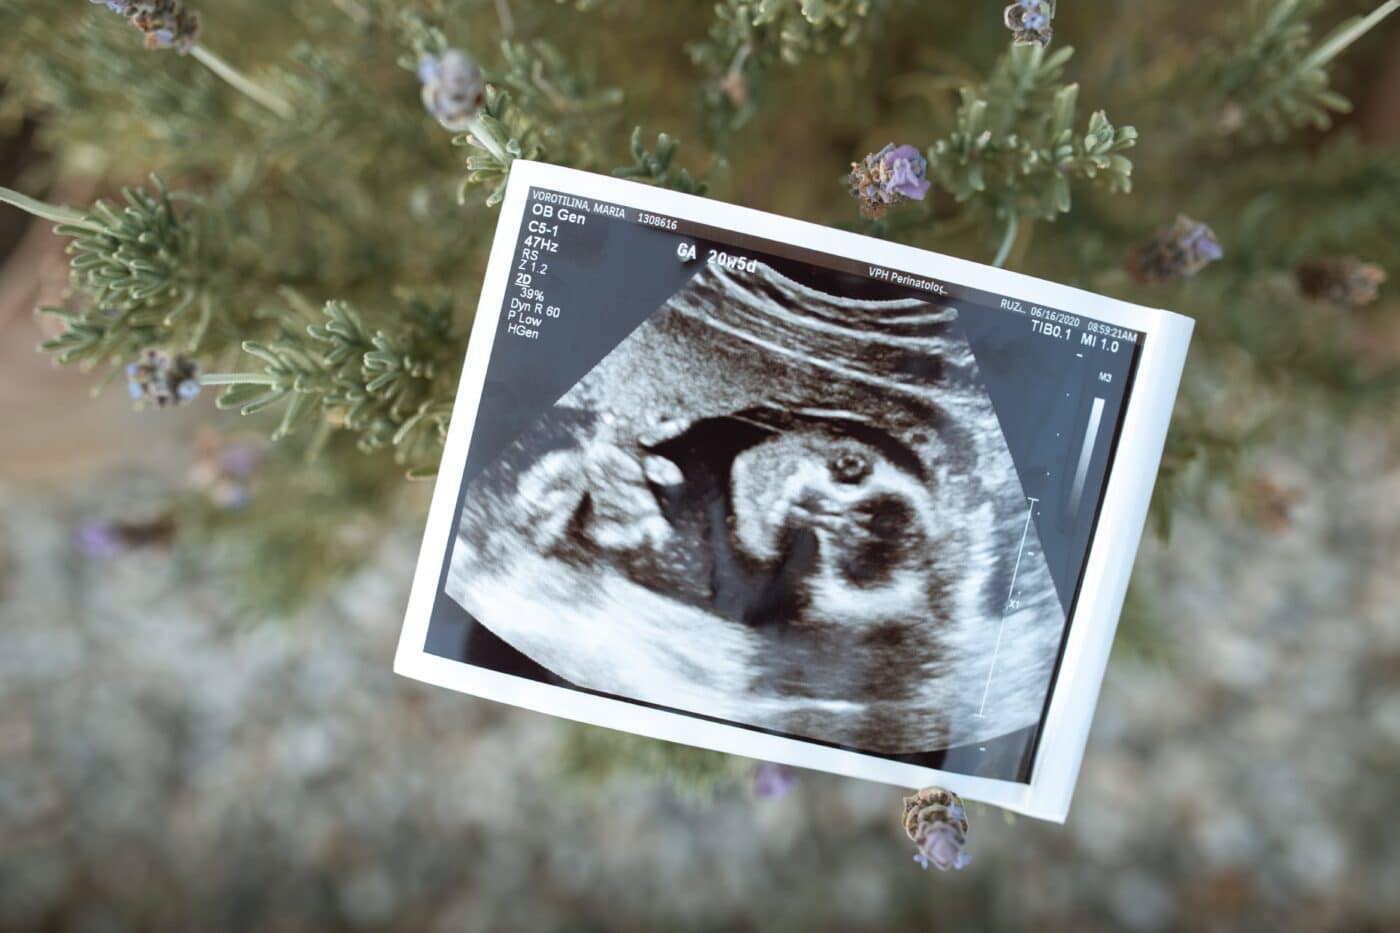

Ciertamente, hasta el momento, el desarrollo del embrión humano no se conoce bien ya que deben transcurrir unas 3 semanas para que se detecten por medios ultrasónicos en el útero materno. Además, no está permitido por la normativa de gran número de países investigar en embriones humanos en etapas posteriores a los 14 días, incluso en los que han sido donados con esa finalidad.